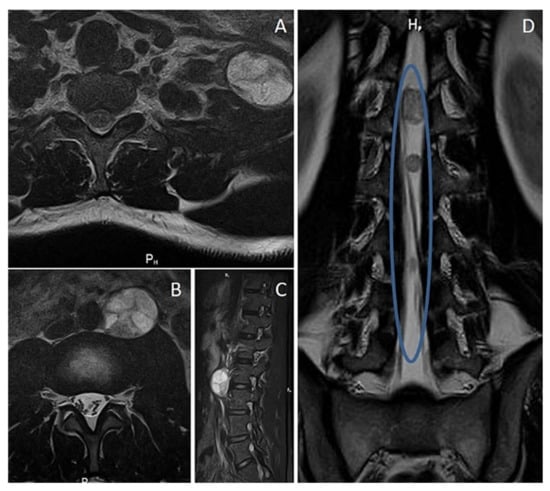

3.3. Plexiform Neurofibroma

3.4. Potential Morphological Pitfalls of Malignancy in Neurofibromas: Cytological Atypia and Hypercellularity